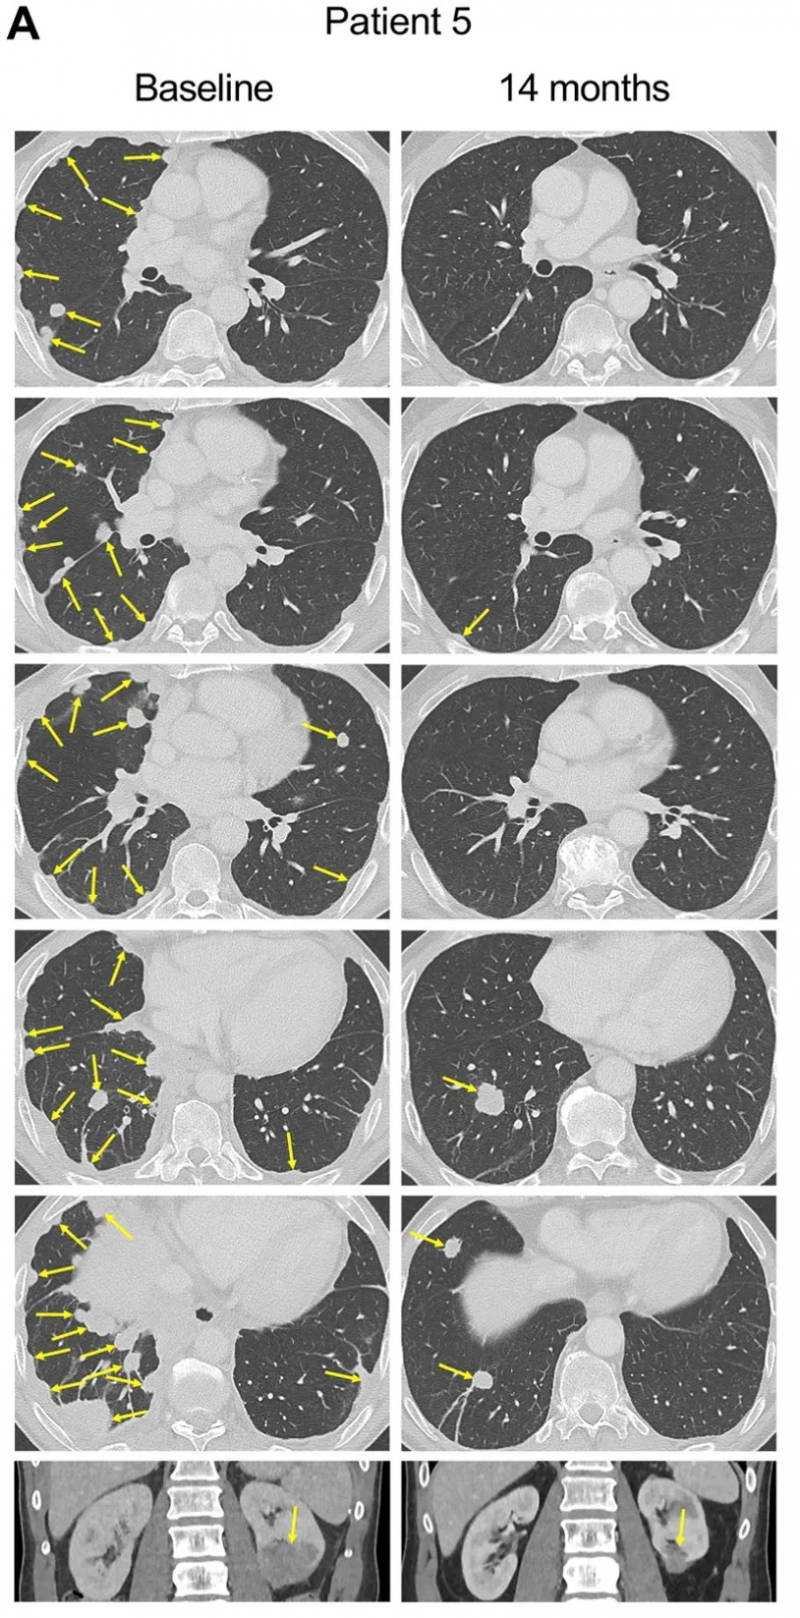

患者5为一例转移性肛门鳞癌患者,伴有90余处转移灶,累及肺部、胸膜、腹膜后、肾脏及骨骼等部位,既往放化疗及PD-1抑制剂治疗均无效。

结果显示:接受E7TCR-T治疗9个月后,80个肿瘤完全消退;治疗14个月后影像学复查仍未检出病灶(详见下图)。

▲图源“Nat Med”,版权归原作者所有,如无意中侵犯了知识产权,请联系我们删除